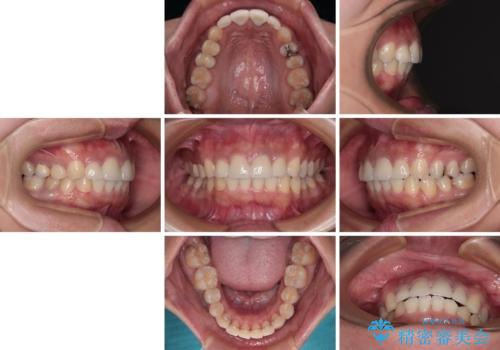

歯列以外に、上顎左右側切歯が矮小歯であり、上顎4前歯は失活していたため、矯正治療で歯列を整えるとともに上顎前歯の幅を調整し、矯正治療後にオールセラミッククラウンにて審美歯科治療を行うこととしました。

下顎の小臼歯を移動しきるのに2年弱の期間を要することとなり、補綴治療も合わせて2年半ほどの治療期間となりました。

口元の印象が大きく改善し、患者様には大変満足していただけました。